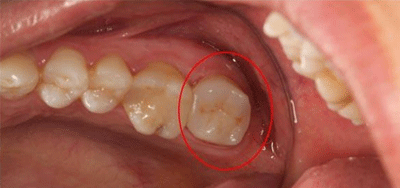

术前照

术前显微镜影像